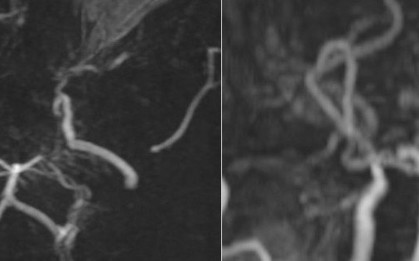

Bệnh viện Đa khoa Thủ Đức (TP.HCM) vừa cứu sống nữ bệnh nhân 52 tuổi bị xuất huyết dưới nhện lan tỏa - tình trạng cấp cứu thần kinh nguy cơ tử vong rất cao.

Chàng sinh viên đang học tại Phú Thọ, sau một tuần đau đầu dữ dội và điều trị tại tuyến dưới không hiệu quả, đã được chuyển lên Bệnh viện Hữu nghị Việt Đức để tiếp tục điều trị.